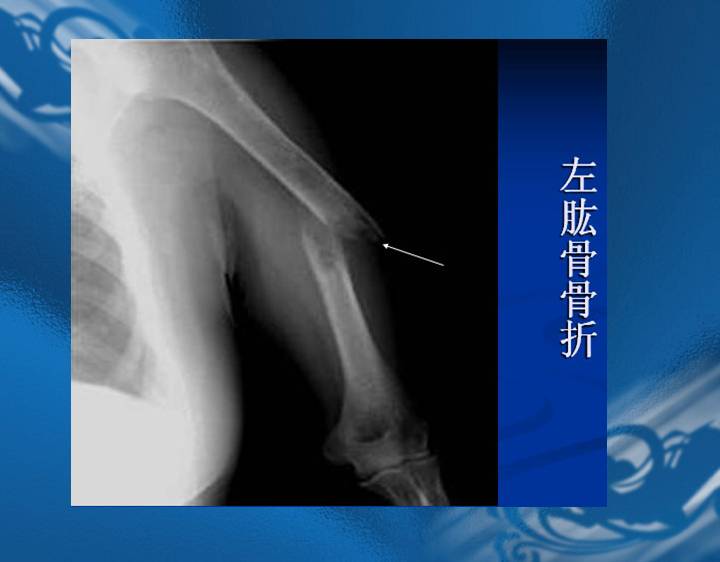

执业医师资格考试“实践技能”影像学辅导资料